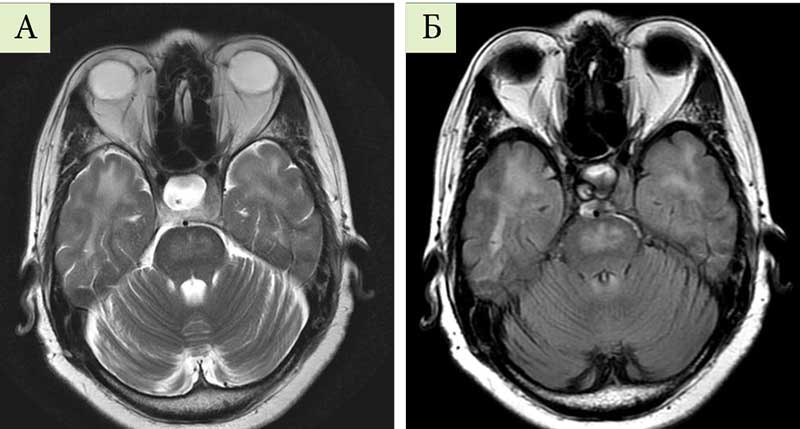

Рис. 2. Фиброколоноскопия пациентки А. 35 лет, от 30.03.2021 г.: солитарная язва прямой кишки при болезни Крона (А – эндоскопическая визуализация,  Б – гистоморфологическая картина)

По результатам проведения фиброколоноскопии от 30.03.2021 г., заподозрен диагноз: «болезнь Крона; заболевание толстой кишки»; по заключению патоморфолога: солитарная язва кишечника с перифокальным воспалением высокой степени активности (рис. 2).